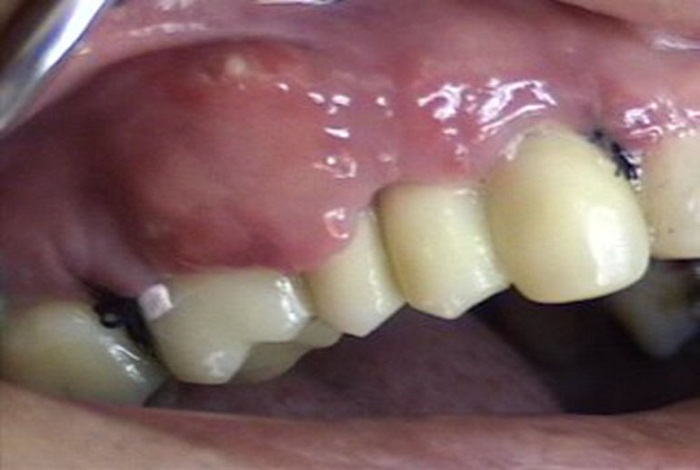

La paciente acudió a control clínico una semana después de la cirugía y se encontró un absceso gingival localizado desde el centro de la cara vestibular del 16 hasta mesial del 13. Presentaba edema, supuración al leve estímulo, dolor a la palpación y fiebre (figura 3).

Se le drenó el absceso a la paciente por medio de una incisión a la altura coronal. En el mismo acto se tomó un cultivo en medio de transporte VMGAIII. Se encontraron los microorganismos Porphyromonas gingivalis (1,66 %), Prevotela intermedia/nigrescens (8,88 %), Tannerella forsythia (0,5 %), Campilobacter spp. (0,5 %), Eubacterium spp. (0,5 %), Fusobacterium spp. (6,66 %), Parvimonas micra (0,05 %) y Eikenella corrodens (6,11 %). A partir de estos hallazgos y la prueba de sensibilidad antibiótica, se prescribió amoxicilina de 500 mg, 1 tableta cada 8 h durante 5 días, más metronidazol de 500 mg, 1 tableta cada 8 h durante 5 días. La paciente regresó a control entre una y 4 semanas después, tiempo al cabo del cual se observó la resolución completa del absceso (figura 4).